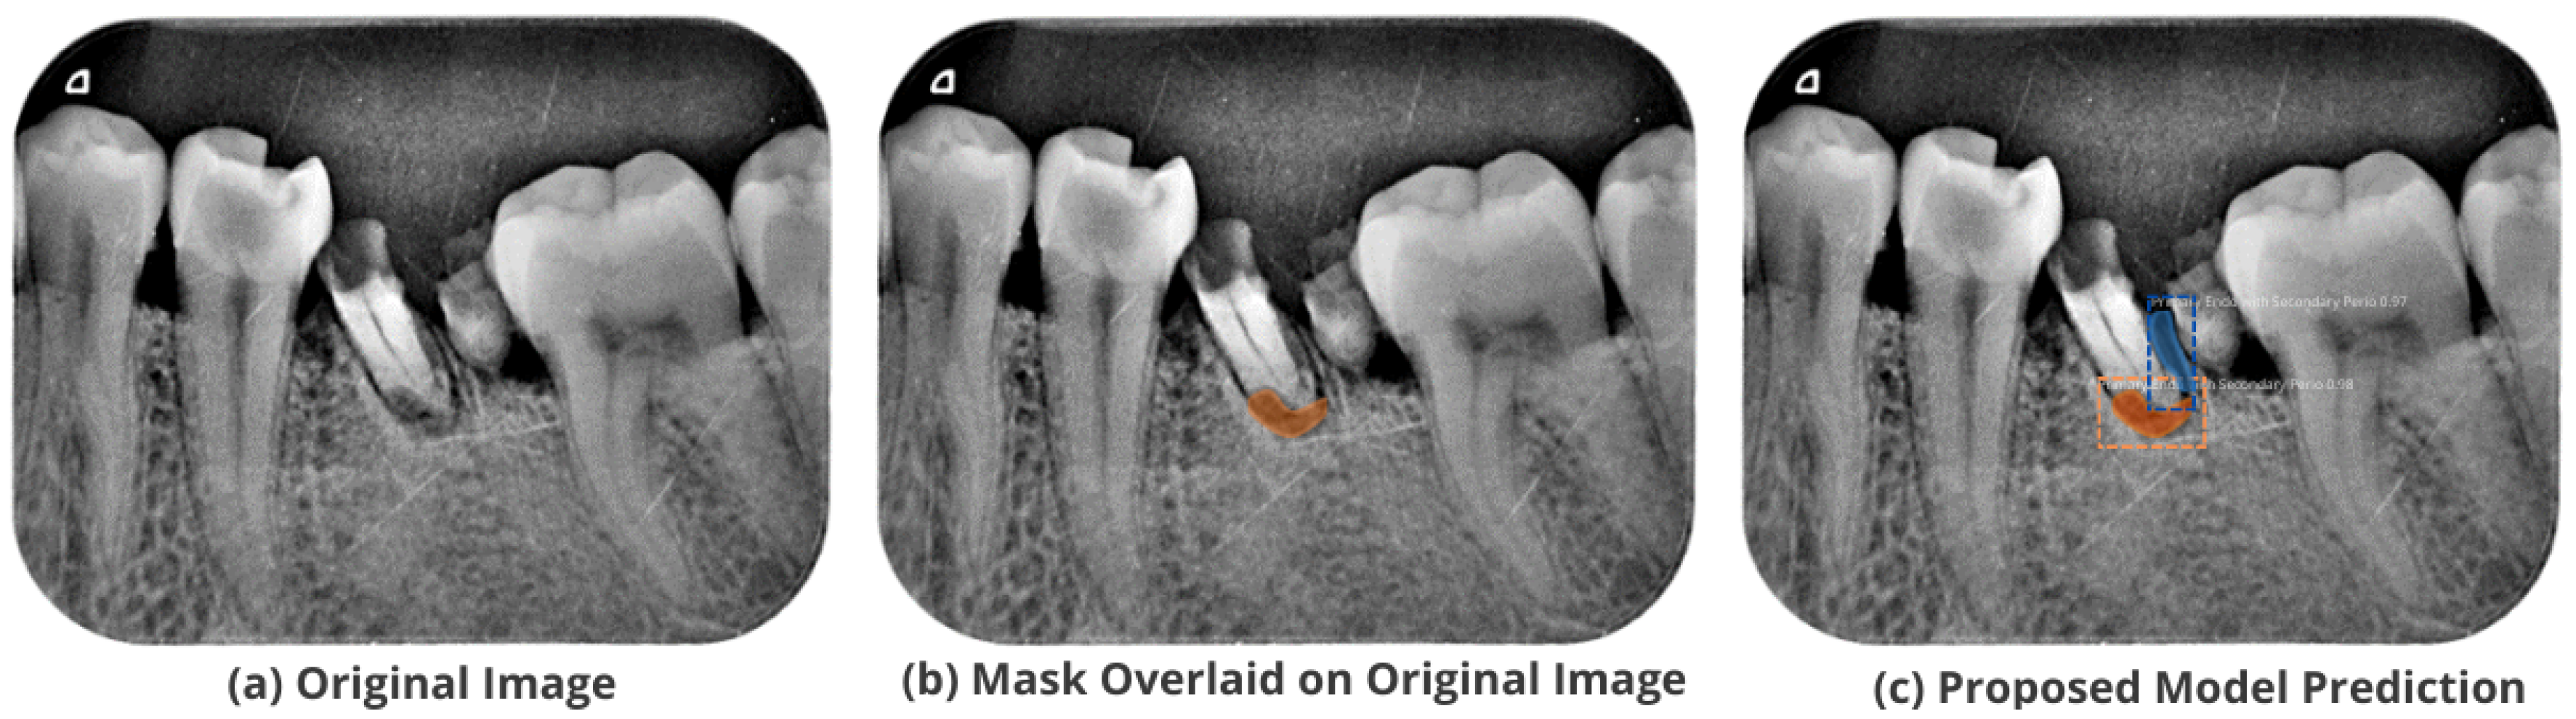

3.5. Comparison with Test Images

The proposed model accurately predicts and localizes the lesions as depicted in Figure 10, Figure 11, Figure 12, Figure 13 and Figure 14. The results indicate that the model makes predictions similar to that of the annotated masks using the periapical radiographic images. Additionally, the proposed model was evaluated based on performance indicators like precision, recall, F1 score, and accuracy for each classified periodontal lesion. The obtained results indicate that the proposed backbone network provides good performance for disease classification. All the test images for the proposed study show a 95% confidence level indicating that the database annotations are in the right direction.

Figure 10.

Test performance for the localization of a ’Primary Endo and Secondary Perio’ lesion.